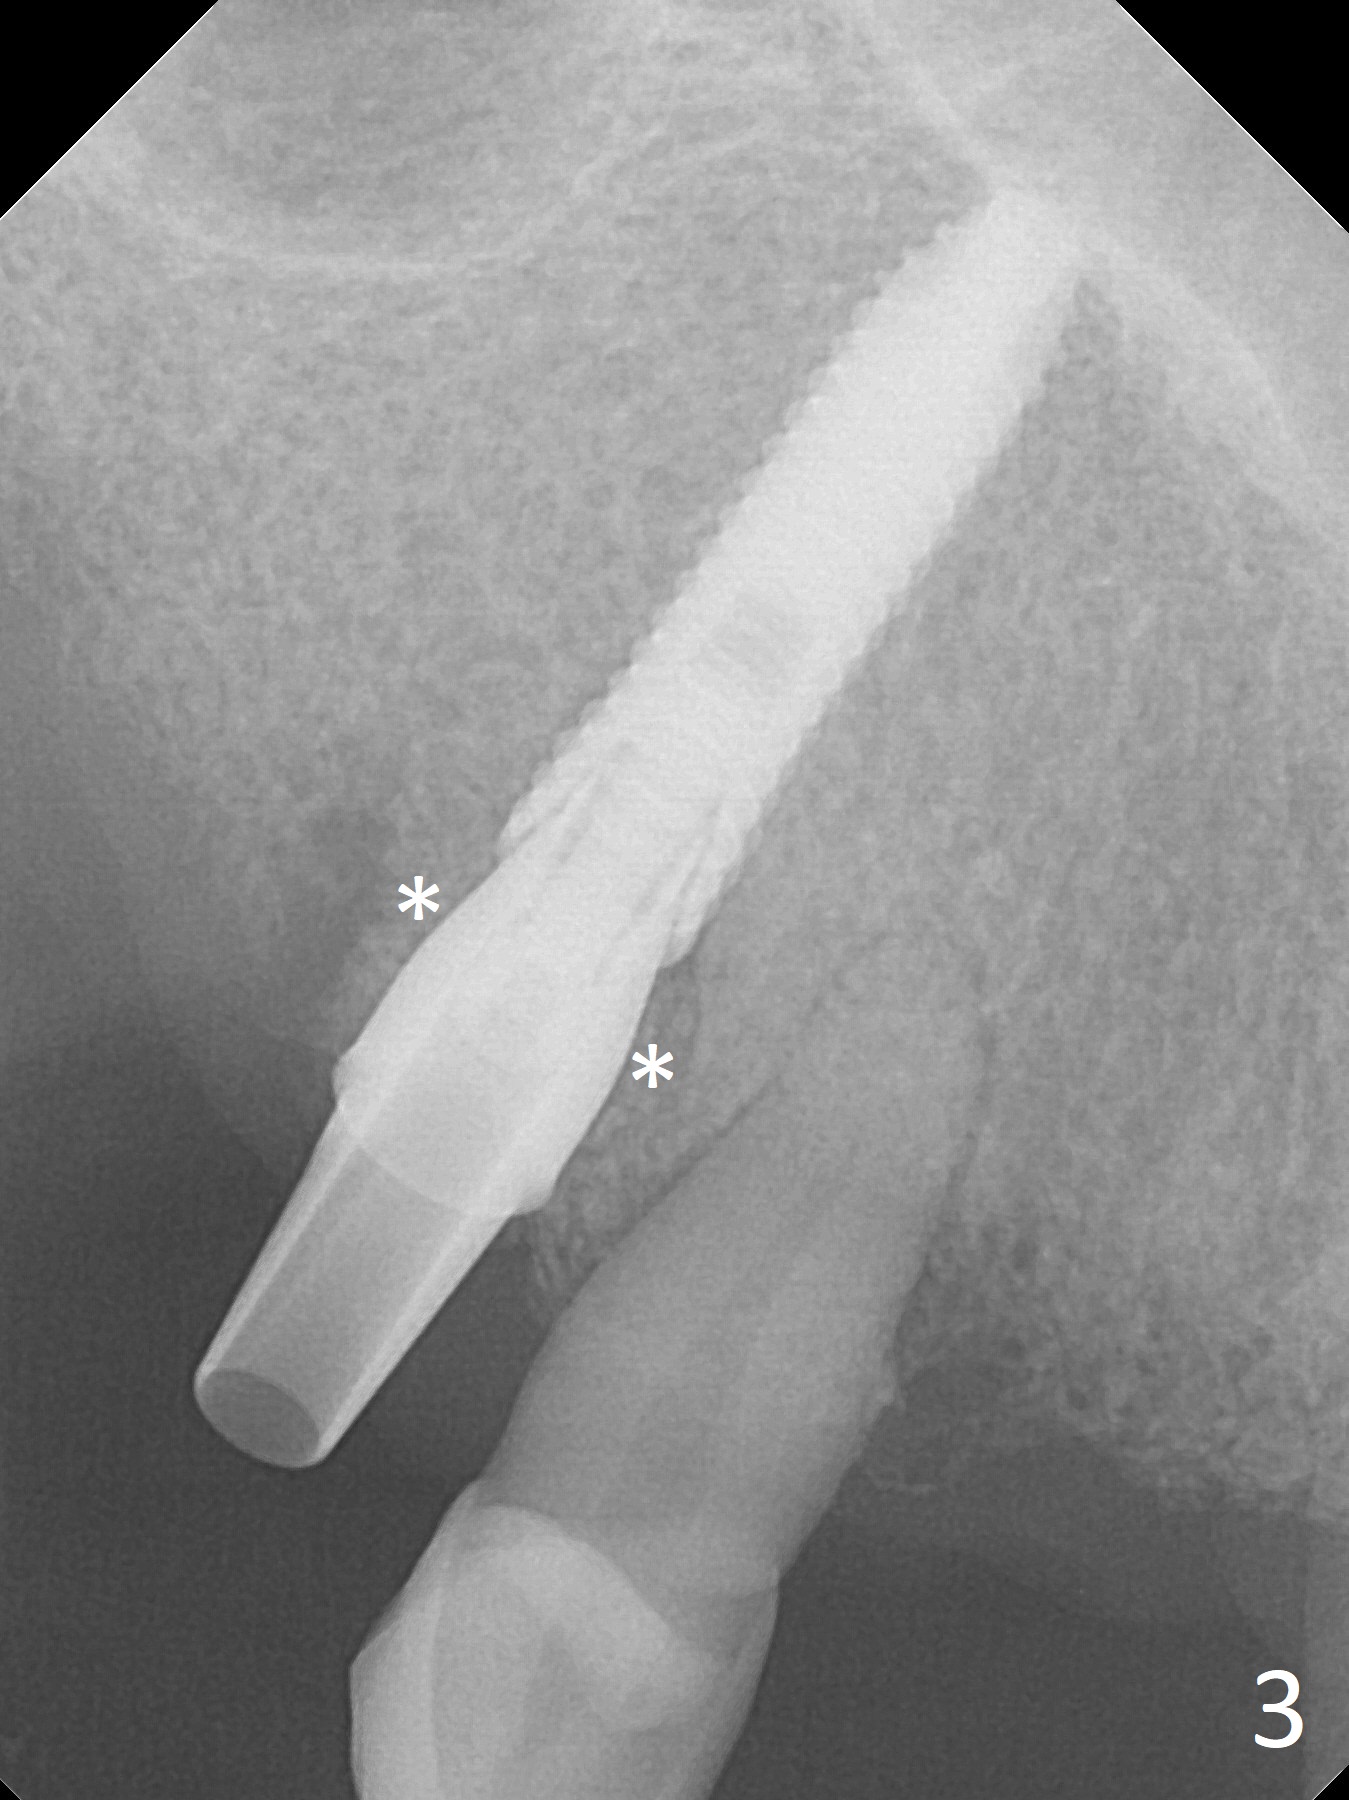

Extraction of the tooth #5 with mobility III reveals no buccal plate and low palatal plate.  Osteotomy starts as palatal as possible (Fig.1).  The bone density is low.  After use of 2.7 mm drill (Fig.2), a 3 mm drill can be inserted into the osteotomy without resistance.  A 4x16 mm implant is placed with insertion torque <30 Ncm.  When an abutment is placed, the implant is found to have been placed distal.   The implant is untorqued for change in trajectory.  When a 4.5x7(5) mm abutment is placed, the abutment turns with the underlying implant (Fig.3).  The former is kept to be turned with a hand driver until the latter is unable to turn.  Following placement of allograft (Fi.g3,4 *), a mini-provisional is fabricated to retain the bone graft and at the same time not to be interfered with when a flipper is in and out.  The bone graft in the former socket gap appears to have integrated into the native one 4.5 months postop (Fig.5).